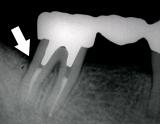

歯槽膿漏・X線写真 | ||

| 歯槽膿漏によって失われた骨(→印の部分)が再生しています。 | ![]() |

![]() |

【術前】 |

【術後】 |